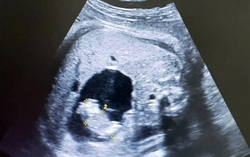

Sức khỏe 14:24 22/09/2025Mang thai vốn dĩ là một hành trình nhiều thử thách. Với chị N.T.X (28 tuổi, Hà Nội), hành trình ấy còn khắc nghiệt gấp bội khi chị mang song thai chung một bánh rau – hai buồng ối, một tình huống thai kỳ tiềm ẩn nhiều biến chứng nguy hiểm.